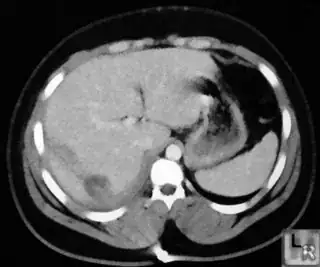

Below are some of the opened and segmented images. Of course there's more to be done in terms of

- separating out the liver region

- generalizing this to a large dataset

but hope this is at least a starting point.

You might be able to narrow down the region or interest by filtering out the darkest and the lightest regions from the segmented image. For this, use the k-means cluster centers, check for the extreme values (max and min) and remove the corresponding k values from the labeled image. Then you can look for large structures to the left of the result image. Worst case, you might get a hole on the left side when the extreme region filtering goes wrong. I've updated the code and results.